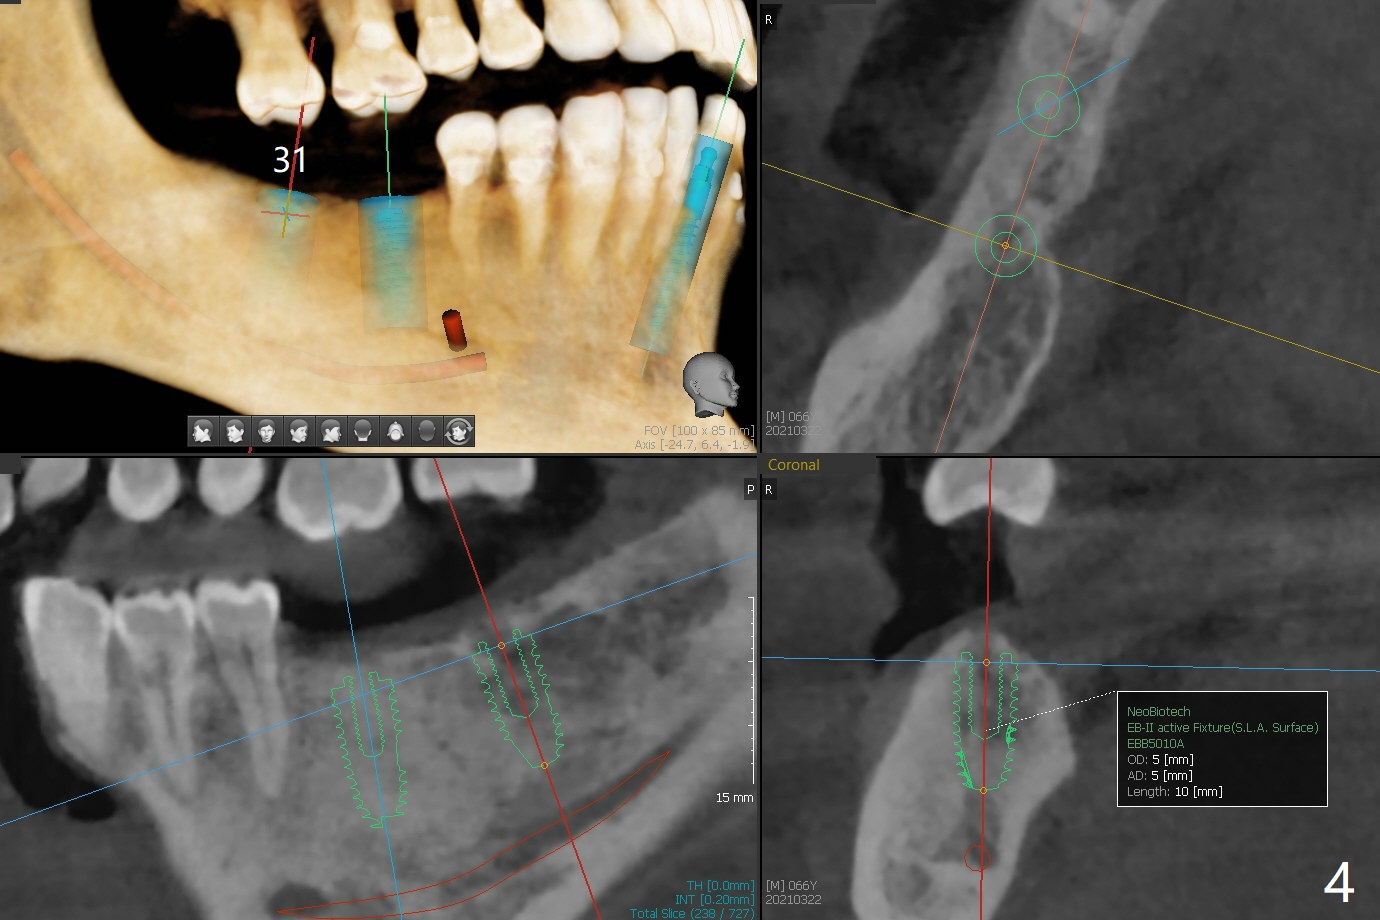

A 66-year-old man requests implant placement at #24, 30 and 31 (Fig.1). Bone loss at #19 and 24 lingual (Fig.2) suggests bruxism. The implant at #24 will be as buccal and mesial (to close the diastema between 24 and 25 (Fig.1 *)) as possible (Fig.2). The vertical space for restoration of 30 and 31 implants (Fig.3,4) is limited; the cusps of the opposing teeth may need to be trimmed.